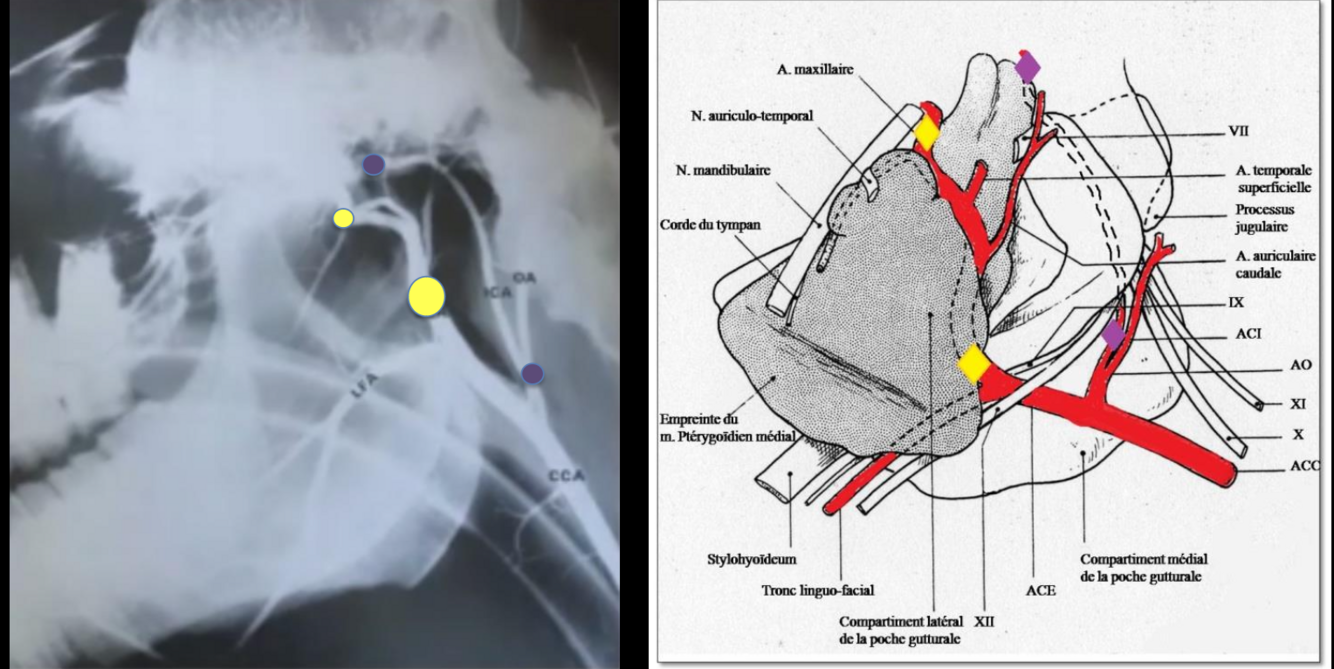

quelles sont les artères importantes qui passent dans la poche gutturale (3) Dans quel compartiment?

a. carotide interne,

a. carotide externe

a. maxillaire

-> dans le compartiment latéral

quels sont les nerfs importants qui passent dans la poche gutturale

trijumeau (5)

facial (7)

vestibulo-cochloaire (8)

nommez une région très importante de la vascularisation de la tête

le cercle de Willis: anastomose de toutes les artères de la tête